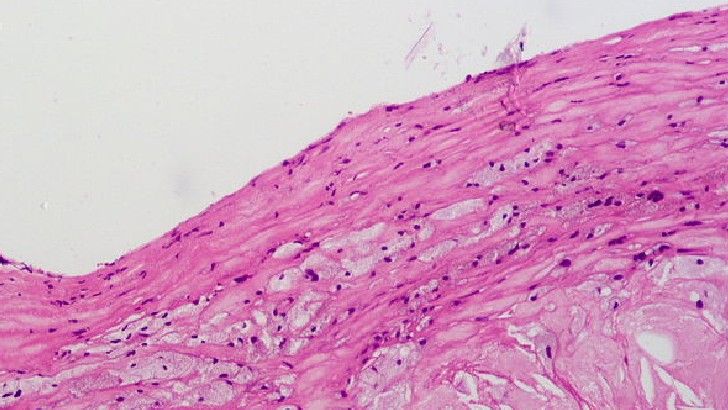

What causes multiple sclerosis symptoms?

Degeneration of the sheath that covers the neurons of the central system and the replacement of this sheath with scar tissue.